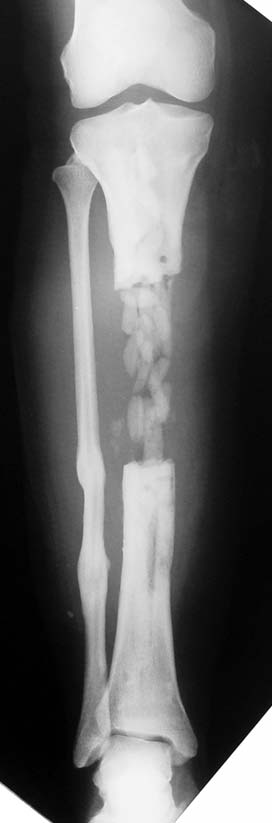

Kronik osteomiyelit, kemik ve yumuşak dokularda nekroza yol açar. Ölü kemik, patojen mikroorganizmalara ev sahipliği yapan bir nidus oluşturur. Konağın savunma sistemleri, mikroorganizmalarla baş etmek için sıklıkla optimal koşullarda değildir. Dolaşım bozukluğu yüzünden enfeksiyon bölgesine antibiyotikler yeterince ulaşamaz. Bu nedenle ölü dokuların ortamdan tamamen uzaklaştırılması gerekir (radikal debridman).

Uygun radikal debridman tüm nekrotik kemik ve yumuşak dokuların çıkartılmasını gerektirir, ve sıklıkla uzuvda instabiliteye neden olur. Kalan kemik ve yumuşak doku defektinin bir şekilde fiksasyonu ve rekonstrüksiyonu gereklidir. İlizarov’un ortaya koyduğu distraksiyon osteogenezi yöntemi, kaynamanın elde edilmesi, deformitenin düzeltilmesi, bacak boy eşitsizliğinin giderilmesi ve segmental defektlerin rekonstrükte edilmesi için başarıyla kullanılmaktadır.